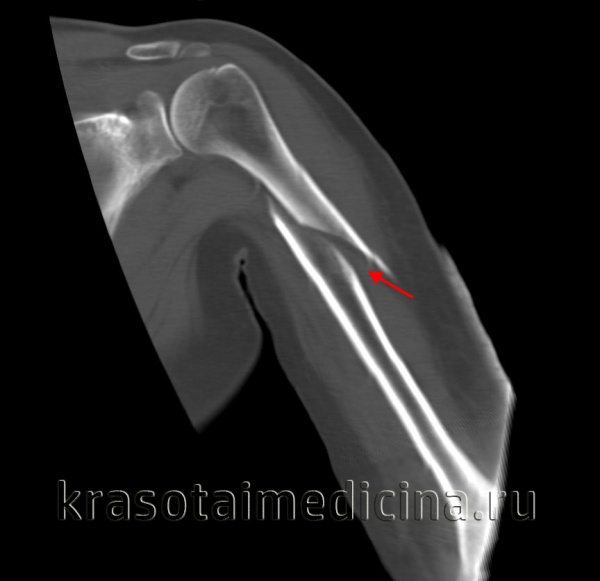

Ещё один клинический пример остеосинтеза тяжёлого перелома мыщелков плеча с использованием пластин с угловой стабильностью Synthes.

Пациентка Х, 54 лет, получила внутрисуставной Y-образный перелом мыщелков плеча. Смещение костных отломков настолько значительно, что диафиз плечевой кости близок к тому чтобы перфорировать кожу.

В случае настолько грубого смещения при первичном осмотре целесообразно выполнить анестезию перелома и устранить смещение с фиксацией конечности в задней гипсовой лонгтеной повязке. После обследования и предоперационной подготовки пациентка взята в операционную. Выполнен остеосинтез при помощи пластин с угловой стабильностью Synthes.

Послеоперационные рентгенограммы показывают, что смещение отломков полностью устранено, нормальные взаимоотношения костей верхней конечности восстановлены.